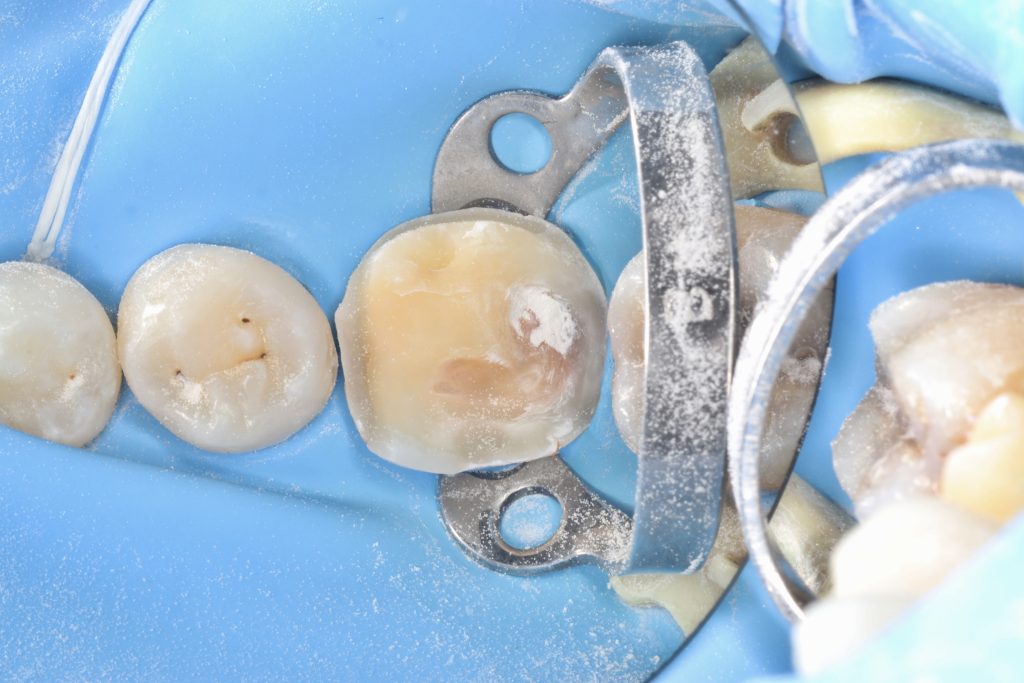

The crack line can be seen in 25x magnification videos.

The pulp vessel structure’s health at 25x magnification led to its closure with MTA.